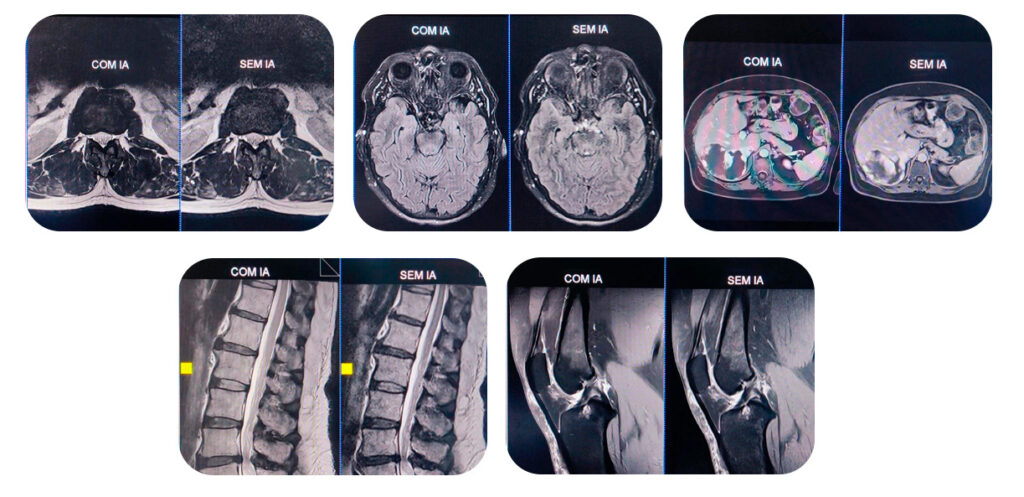

Nossa Ressonância Magnética agora conta com integração à Inteligência Artificial (IA), uma tecnologia que representa um verdadeiro salto no diagnóstico por imagem.

Imagens com definição superior

Maior nitidez e riqueza de detalhes para um diagnóstico ainda mais preciso;

Com a nova tecnologia, os exames tornam-se mais rápidos, o tempo dentro do equipamento é reduzido e o paciente vivencia uma experiência mais confortável e tranquila. As imagens geradas passam a ter definição superior, com mais nitidez e riqueza de detalhes, facilitando a visualização de estruturas e lesões.

Além da agilidade, a Inteligência Artificial aprimora a definição das imagens, destacando estruturas anatômicas e possíveis alterações com maior clareza.